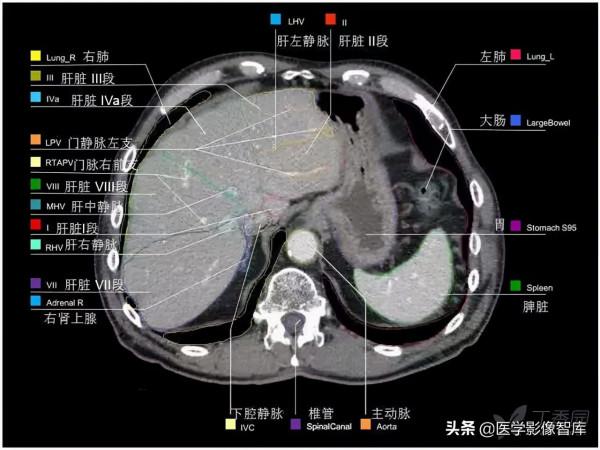

腹部CT